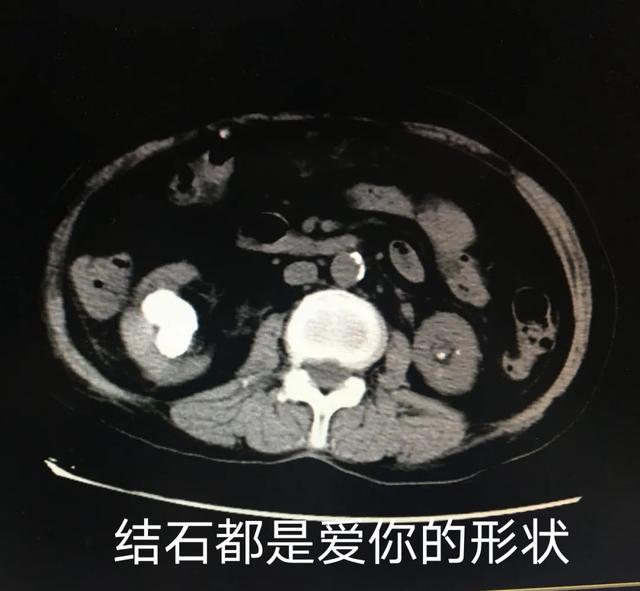

(上图为右肾铸形结石,下图为左侧脑出血)